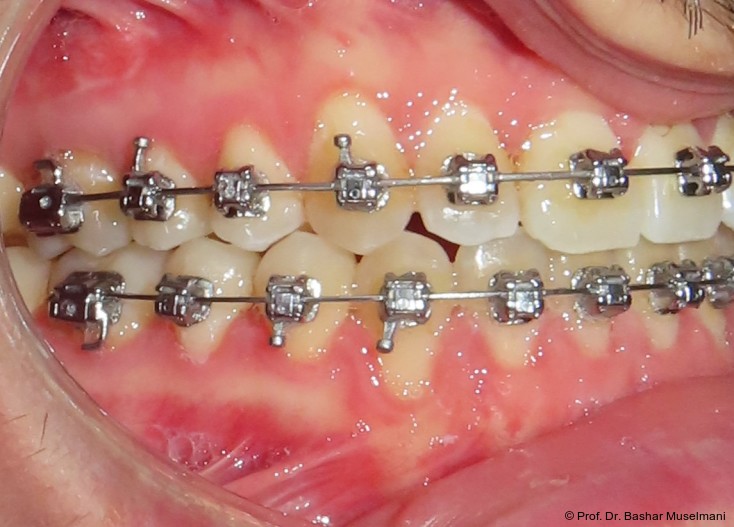

Apparative Versorgung

Die Behandlung erfolgte mittels einer festsitzenden Multibracketapparatur unter Verwendung passiver selbstligierender Brackets (Damon Ultima System) im Ober- und Unterkiefer.

Die Wahl des Systems erfolgte mit den Zielen,

• die Torque-Expression effizient auszuschöpfen,

• eine kontrollierte dentoalveoläre Kompensation zu ermöglichen,

• unerwünschte Nebenwirkungen während der Klasse III-Korrektur zu minimieren.

Zur sagittalen Korrektur wurden intermaxilläre Klasse III-Gummizüge eingesetzt.

Bracketpositionierung und Torque-Strategie

Oberkiefer

• Zähne 12–22: Brackets mit Retroklinations-­Torque

• Zähne 13 und 23: Brackets mit proklinationsförderndem (Brocline-)Torque

Ziel war die kontrollierte Retrusion der oberen Front bei gleichzeitiger Sicherung der Eckzahnbreite.

Unterkiefer

• Zähne 33–43: Brackets mit proklinationsförderndem Torque

Hierdurch sollte eine gezielte Proklination der unteren Front zur Verbesserung des Overjets und der sagittalen Verzahnung erreicht werden.

Zu Beginn der Nivellierungsphase wurden in beiden Kiefern 0.013" CuNiTi-Bögen eingesetzt (Abb. 4a–e).